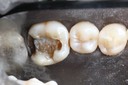

Gary Umeda #18-19 prep